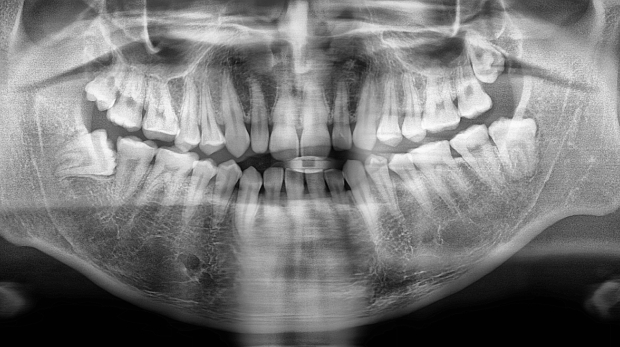

박** 환자분 (오른쪽 상하악 사랑니 동시 발치 케이스)

상악의 경우 단순매복으로 발치 및 동시에 하악 잇몸뼈에

깊게 박혀잇는 고난이도 케이스, 잇몸절개 후 치아 분리하여

발치하였으며